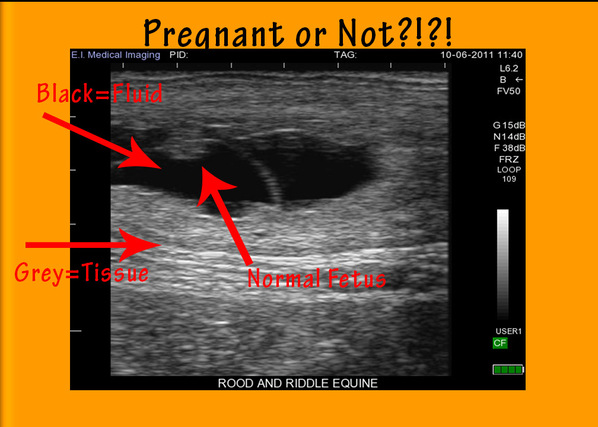

Black and white sheds light.

In our Technicolor world, your client might be surprised to see that ultrasound images are in shades of black, white and gray. You are comfortable with this monochromatic visual, but the typical horse owner may be skeptical about contemporary technology that isn’t using full, living color! Tell him that light and dark are all you really need to see on the monitor, because the intensity of the returning signal translates into a level of brightness on the screen. The more dense the tissue, the brighter the image; so fluid appears black, dense materials such as bladder stones appear bright white, and the internal organs and structures will appear varying shades of grey. This baseline information will help your client to begin to understand what the ultrasound image means.

Many horse owners have a keen interest in equine physiology and it’s safe to say that goes double for people who breed their mares. But, don’t mistake that fascination with any great depth of veterinary knowledge. You know how organisms function, but take care not to overwhelm your client with all the details. Instead, point out basic, recognizable structures such as the beating heart of a fetus, the unique shape of a kidney, or flecks of pus floating around in an abscess.